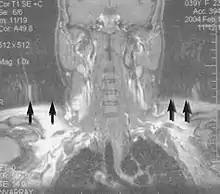

Neuroimaging

MRI is the investigative tool of choice for neurological cancers over CT, as it offers better visualization of the posterior cranial fossa, containing the brainstem and the cerebellum. The contrast provided between grey and white matter makes MRI the best choice for many conditions of the central nervous system, including demyelinating diseases, dementia, cerebrovascular disease, infectious diseases, Alzheimer's disease and epilepsy.[20][21][22] Since many images are taken milliseconds apart, it shows how the brain responds to different stimuli, enabling researchers to study both the functional and structural brain abnormalities in psychological disorders.[23] MRI also is used in guided stereotactic surgery and radiosurgery for treatment of intracranial tumors, arteriovenous malformations, and other surgically treatable conditions using a device known as the N-localizer.[24][25][26] New Artificial intelligence in healthcare tools have demonstrated higher image quality and morphometric analysis in neuroimaging with the application of a denoising system.[27]